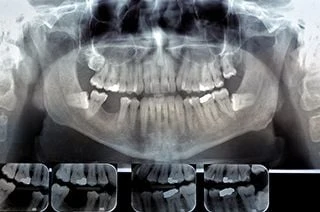

digital x-rayX-rays are one of the most important parts of a dental exam, and can help medical professionals detect problems long before they are visible to the naked eye, including early tooth decay, gum disease, abscesses, and abnormal growths.

Digital X-rays are obtained by putting a small electronic sensor in the mouth, and captured images can be pulled up instantly on a computer screen.

Unlike traditional X-rays that require an intermediary chemical process, your dentist can abstain and evaluate your X-rays almost instantly.

Digital X-ray images are clearer than traditional X-rays and your healthcare provider can zoom in and out, making it easier for them to detect potential problems.

Compared to traditional X-rays, digital X-rays reduce your exposure to radiation by up to 90%. Even though risk is reduced, there is still a slight risk that radiation from X-rays will cause cellular changes that may lead to future disease. Their benefits outweigh their risk, which is why they are so commonly used. Talk to your healthcare provider if you have questions about your safety, or why an X-ray is recommended for you.